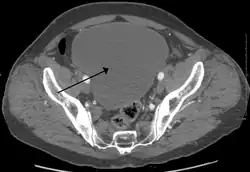

| Urinary retention with greatly enlarged bladder as seen by CT scan. | |